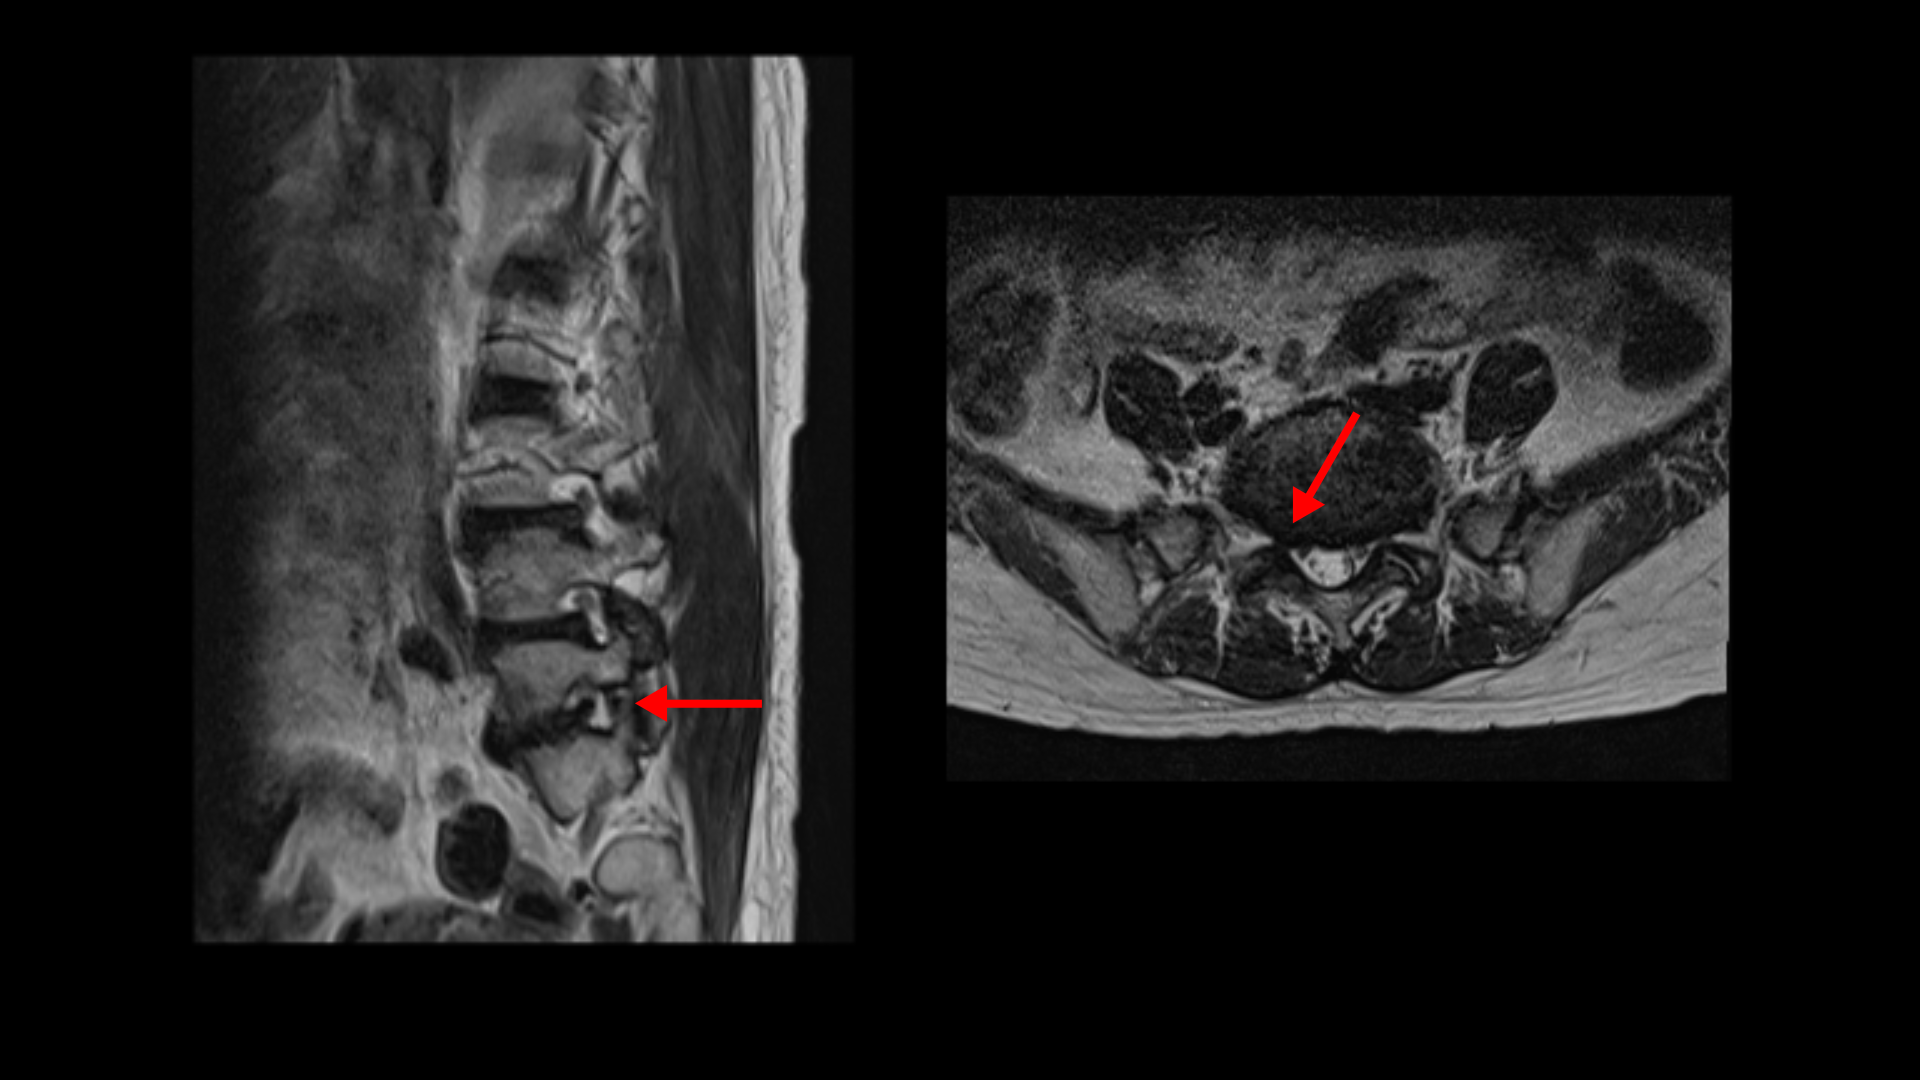

이분 MRI를 보면 3마디에 퇴행성디스크가 밀려 나와 있습니다.

또 3번 4번에는 척추전방전위증이 있습니다.

이 전방전위증 때문에 척추관에 중심성 협착도 있습니다.

4번 5번 디스크가 중앙에서 우측으로 약간 밀려 나와있고

>또 5번 1번에서는 신경이 빠져나가는 오른쪽 추간공이 약간 좁아져 있습니다.